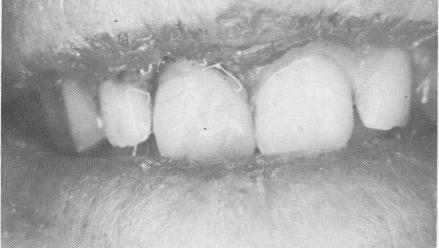

The restorations were fabricated as one-piece castings of two bicuspid acrylic-over-gold crowns (Fig. 8-10). The crowns were tried in the mouth for accuracy of interproximal fit, and all occlusal adjustments were made.

The crowns were cemented over the two protruding implant shafts in the same manner as in Case 1 (Fig. 8-14). However, whereas the implants in Case 1 were left completely unsplinted from the very onset, in this case the implants were immediately ligated to neighboring teeth with soft .010 stainless steel ligature wire (Fig. 8-15). The occlusion once again was carefully checked and all necessary adjustments were made (Fig. 8-16). A post-operative lateral plate roentgenogram of the completed case shows all implants in place (Fig. 8-17).